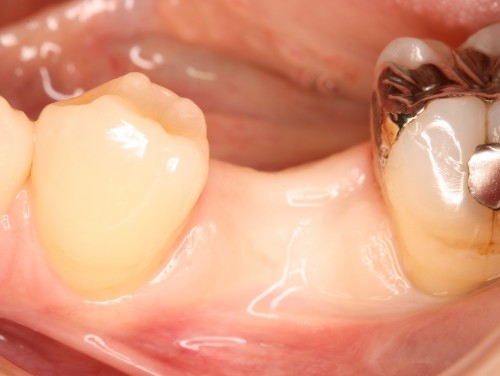

エナメル質に達するむし歯

光重合レジン充填・他

象牙質に達するむし歯

光重合レジン充填・部分的な詰め物(型どりを要す物)

CO:初期むし歯

C1:エナメル質に達するむし歯

C2:象牙質に達するむし歯